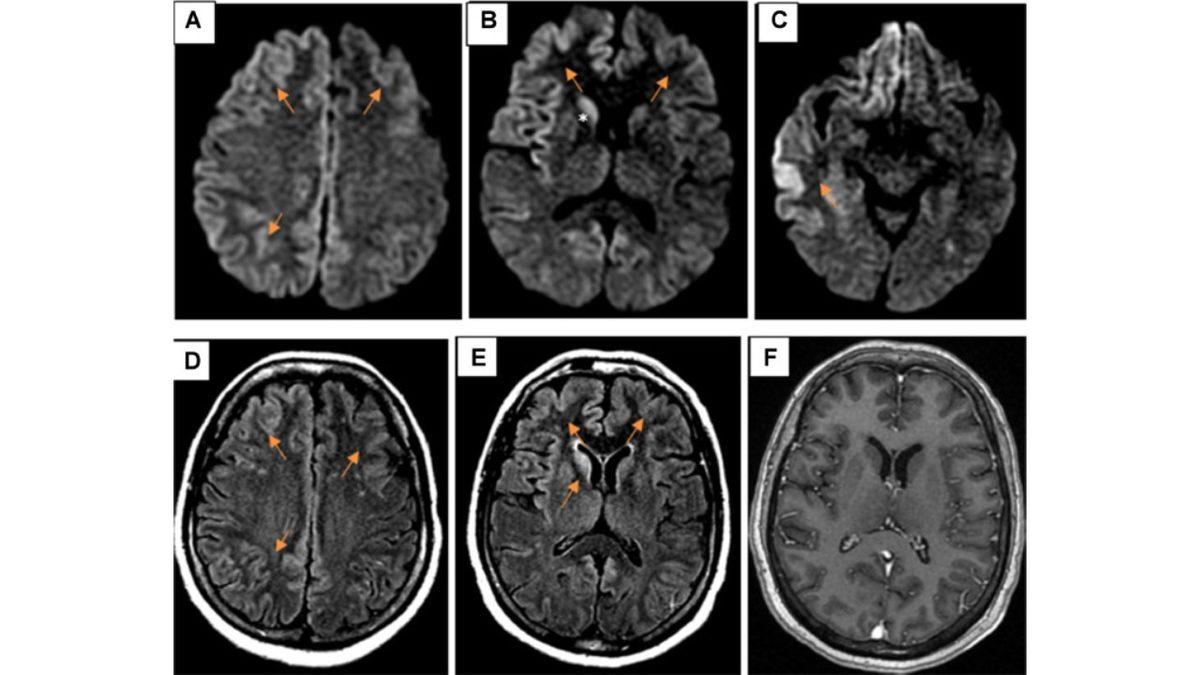

Öte yandan bu rahatsızlığa, beyindeki prionlar yani anormal proteinler sebep oluyor. Bu proteinler de dokularda ne yazık ki geri döndürülmesi imkânsız hasarları beraberinde getiriyor.

Aynı zamanda beynindeki çoğu nöronun düzgün çalışmamasına ve ölmesine sebep olan sünger benzeri delikleri yaratıyor.